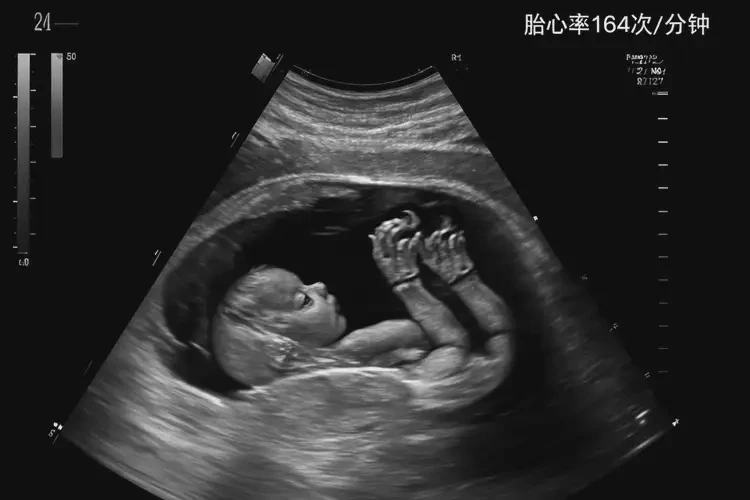

孕27周1天胎心164還要保胎嗎

胎心164次/分鐘在孕27周1天屬于正常范圍,通常無(wú)需特殊保胎措施。

胎心率是指胎兒心臟每分鐘跳動(dòng)的次數(shù),是評(píng)估胎兒健康狀況的重要指標(biāo)之一。在孕27周1天,胎兒的胎心率正常范圍通常在120-160次/分鐘之間。雖然164次/分鐘略高于正常范圍的上限,但并不意味著一定需要采取保胎措施。以下是詳細(xì)的分析和建議:

孕27周1天胎心164還要保胎嗎(圖1)